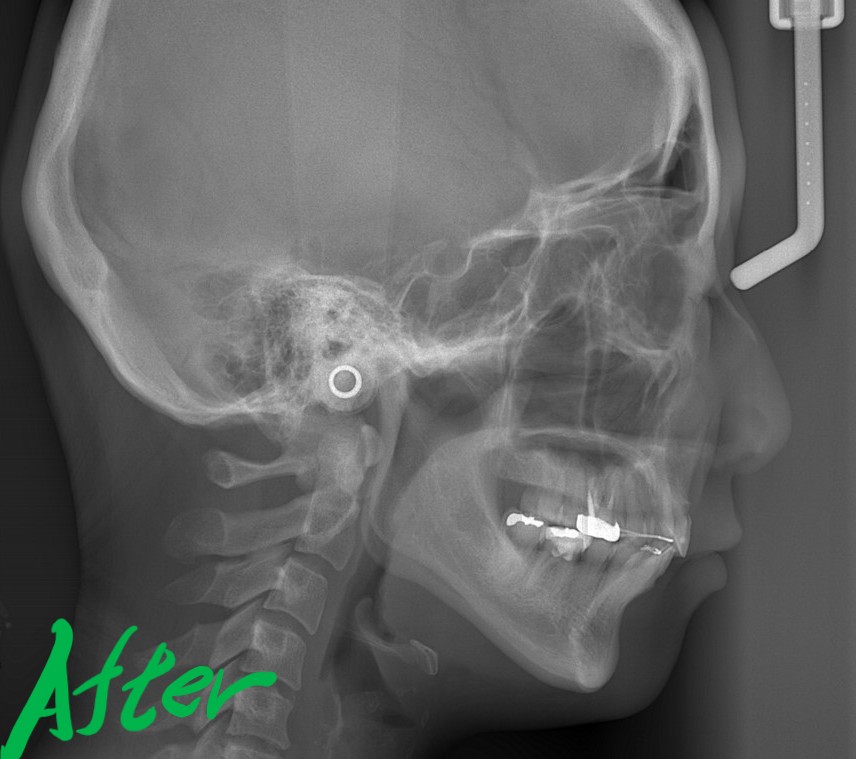

【After】

レントゲン写真で確認すると、